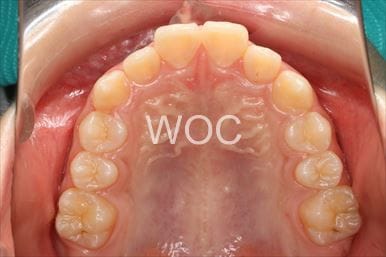

治療前1

治療前2

治療前3

治療前4

治療前5

- 年齢:20歳女性

- 主訴:出っ歯が気になる

- 基本矯正料金:120万円

- 治療期間:1年7ヶ月

- 抜歯部位:上顎両側第一小臼歯